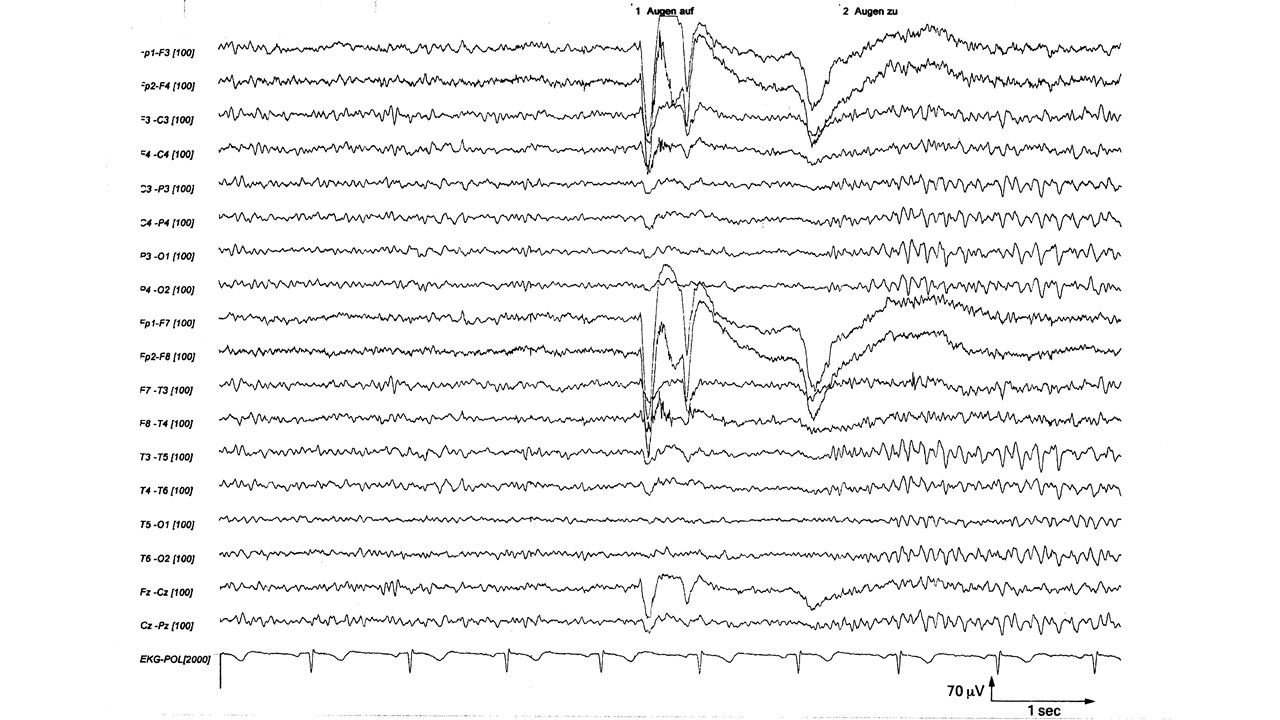

folie564.jpg